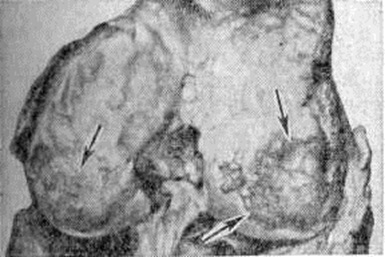

Рис. 3.

Макропрепарат головки бедра с проявлениями болезни Кашина — Бека: видна изъеденность суставного хряща (указано стрелками) и деформация головки бедренной кости.

Патологическая анатомия процесса в динамике не изучена. Однако картины его исходов позволяют считать, что в основе болезни лежит механическая неполноценность хрящевого вещества, обусловленная отсутствием в организме субстанции, необходимой для формирования хряща, или, наоборот, поступлением в организм веществ, нарушающих этот процесс. На первый план выступают дистрофические изменения хряща мелких и крупных суставов конечностей, возрастающие соответственно степени болезни. Суставной хрящ мутнеет, истончается, иногда появляются узуры, проникающие в субхондральные отделы кости. Поверхности суставов неровные, шероховатые (рисунок 1). В наиболее нагружаемых участках хрящ стирается, отслаивается, обнажая кость (рисунок 2). Иногда суставная поверхность полностью лишается хрящевого покрытия и представляет собой отшлифованную кость. Суставные концы деформируются. В длинных костях образуются краевые костные разрастания, характерные для деформирующего артроза. В редких случаях наблюдается уплощение головок плечевых и бедренных костей (рисунок 3), которые могут принимать грибовидную форму, разрастание ворсин синовиальной оболочки с образованием рисовых тел. В полостях суставов могут быть свободные хрящевые и костные суставные тела. В грудном отделе позвоночника может развиваться кифоз, сколиоз, в поясничном — лордоз, обусловленный деформациями позвонков. Высота позвонков уменьшена вследствие остеопороза. В дисках появляются трещины, щели с гомогенным или крошковатым детритом. Со временем развиваются явления деформирующего спондилёза с характерными для него краевыми костными разрастаниями. Данных по микроскопическому исследованию костной системы не много, и относятся они лишь к исходам процесса у взрослых. В суставных хрящах обнаруживаются бесклеточные некротические участки, уменьшение базофилии межклеточного вещества, снижение содержания в нем кислых сульфатированных мукополисахаридов, что вызывает демаскирование хондриновых волокон, растрескивание и глыбчатый распад его.